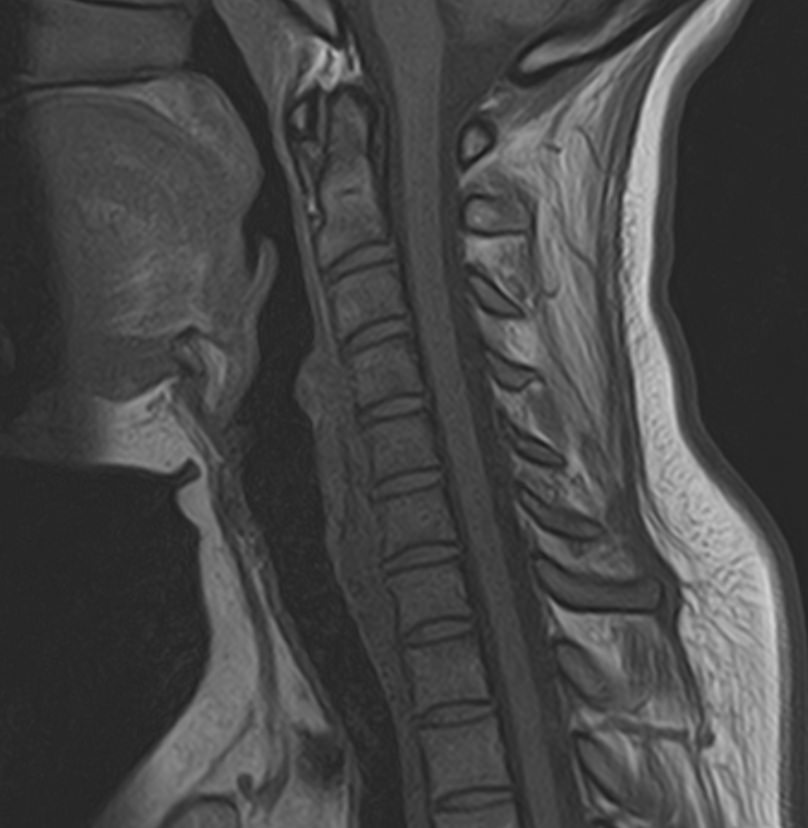

В клинике «Доступная медицина» можно пройти комплексное обследование, включающее в себя два протокола сканирования близко расположенных друг от друга анатомических областей – шейного отдела позвоночника и головного мозга. Метод комплексного обследования оценивает состояние всех структур головного мозга и самого верхнего сегмента позвоночного столба, который включает в себя 7 шейных позвонков, спинной мозг с отходящими от него нервными корешками и окружающими мягкими тканями.

Шейный отдел позвоночника испытывает повышенные нагрузки, подвержен травмам и развитию различных заболеваний. При этом патологические процессы в шейном отделе позвоночника могут нарушать работу головного мозга.

Так, например, опухоли и дегенеративно-дистрофические заболевания шейного отдела позвоночника могут привести к ухудшению кровоснабжения головного мозга и стать причиной появления различных неврологических симптомов. Поэтому бывает важно комплексно визуализировать эти анатомические структуры. Также при травмах головного мозга и шейного отдела позвоночника необходимо одномоментно оценить состояние этих анатомических областей, особенно в ходе предоперационной подготовки, а также в дальнейшем отслеживать динамику состояния структур в послеоперационном периоде и на фоне реабилитационных мероприятий.

Сканирование проводится на современном высокопольном магнитно-резонансном томографе закрытого типа TOSHIBA VANTAGE TITAN 1,5 Тесла. Магнитно-резонансный томограф производит послойное сканирование исследуемой зоны в разных плоскостях, затем при помощи компьютерных программ преобразует полученные данные в трехмерные изображения с высокой степенью детализации.

• остеохондроз, спондилоартроз, спондилез, межпозвонковые грыжи, унковертебральный артроз, сколиоз, усиленный или выпрямленный лордоз как нарушение статической функции позвоночника, травмы, аномалии позвоночника.